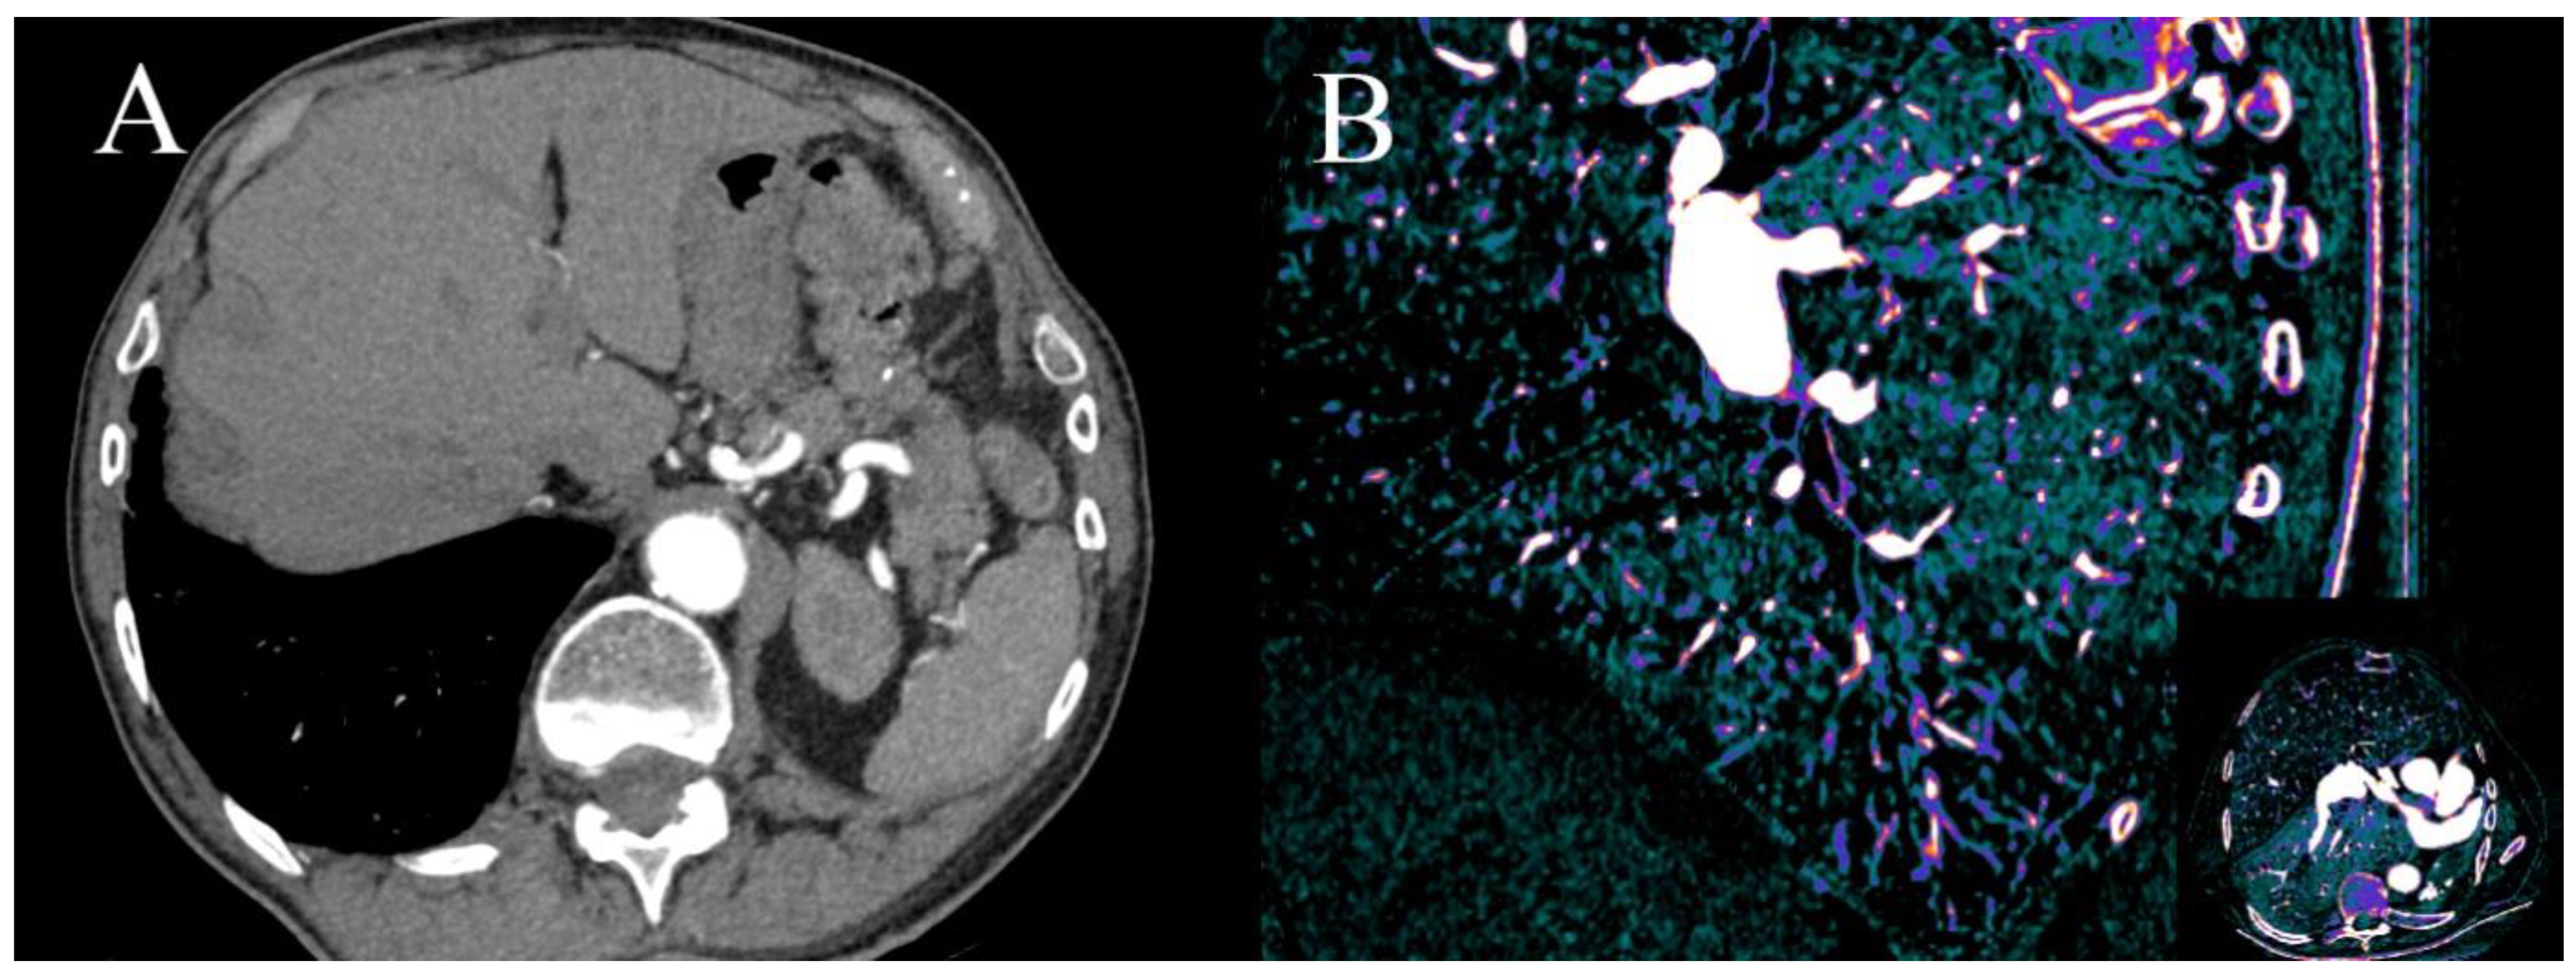

There are three causes of contrast filling defects of heart chambers in coronary CTA: a thrombus, a tumor or a blood flow artefact. The first two require further diagnostic investigation due to different treatments. The most common location of contrast filling defects in patients with atrial fibrillation is the left atrial appendage (LAA); it is also the most common location of intracardiac thrombus. Definite differentiation is possible by performing an additional scan in the venous phase but has the disadvantage of additional radiation dose; definite differentiation can also be achieved by transesophageal echocardiography (TEE). DECT, by using low-energy VMIs or iodine(water) maps can detect even minimal concentrations of iodine in LAA and exclude the presence of thrombus. The measurements of iodine concentration are more accurate than the density of LAA, as it is carried out in SECT (Figure 7A–D) [9,64], and as proven by Hur et al., using 1.74 mg I/mL as the cutoff value for thrombus has 100% specificity. The third cause of the filling defect is the presence of a tumor in the chamber of the heart. As proven by Hong et al., it is possible to differentiate tumors and thrombus using dual-energy coronary CTA by measuring the iodine concentration [65,66].

Figure 7.

(A–D). Case of patient with chronic atrial fibrillation after 3 unsuccessful ablations, currently admitted due to chest pain. Coronary CTA was performed to roll out coronary artery stenosis. Differentiating thrombus and filling defect of LAA using iodine concentration is much more specific and sensitive than the use of Hounsfield unities ratio, as proven by Hur et al. [64]. (A)—Histogram of iodine concentration in ROIs; (B)—map iodine(water) shows lower concentration of iodine in LAA of about 4.1 mg/mL, meeting the criteria for circulatory stasis by Hur et al.; (C,D)–70 keV VMI with color overlay of iodine(water) map. (D)–in log axis of LAA. In the lower right corner of sub-image B-C-D information about viewpoint.